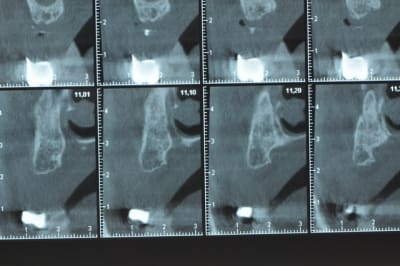

Ce n'est pas vraiment un consensus mais plutot du bon sens. Si tu as une crête en profil de lame de couteau cela signifie que tu as une fusion des corticales vestibulaire et palatine et donc absence de spongieux, ce qui comme tu le sais n'est pas indiqué en implanto (cj os de marbre par exemple)

Il me semble que Palti ou encore Szmukler-Moncler recommandent un minimum de 2-3mm. Si c'est plus fin, greffe d'apposition et GBR.

Dans ton cas il te faudrait abaisser la crête de 3 bons mm pour arriver à cette épaisseur.

Ce n'est pas vraiment un consensus mais plutôt du bon sens. Si tu as une crête en profil de lame de couteau cela signifie que tu as une fusion des corticales vestibulaire et palatine et donc absence de spongieux, ce qui comme tu le sais n'est pas indiqué en implanto (cj os de marbre par exemple)

Il me semble que Palti ou encore Szmukler-Moncler recommandent un minimum de 2-3mm. Si c'est plus fin, greffe d'apposition et GBR.

Dans ton cas il te faudrait abaisser la crête de 3 bons mm pour arriver à cette épaisseur.

D’accord sur les 2-3mm c’est la sécurité en dessous c’est plus hot.